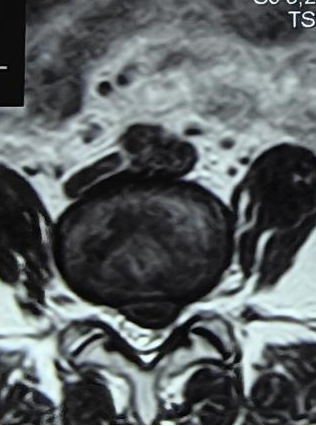

什么是腰椎间盘突出症?

腰椎间盘突出治疗

椎间孔镜手术是什么?